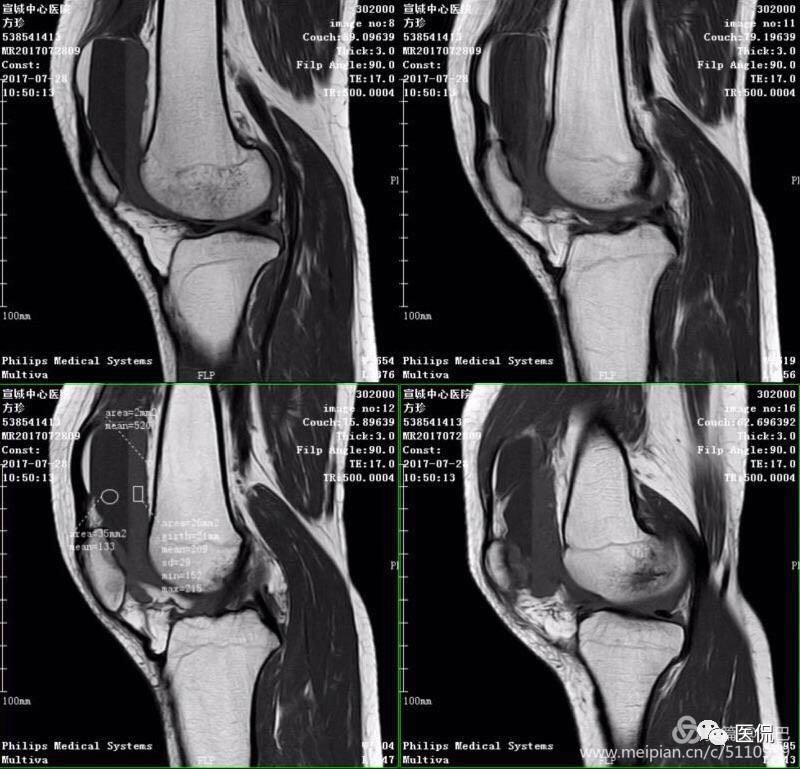

MR表现

1、单液-液平面:上层呈短T1、长T2信号、T2压脂像低信号、Pd像呈高信号;下层呈中等T1、T2信号、T2压脂像和Pd像呈较高信号。

创伤性关节积脂血症MR影像表现的意义

1、通过不同成像序列及不同扫描方位成像,不仅能够准确地显示单液-液平面、双液-液平面和多液-液平面,明确地诊断创伤性关节积脂血症,且在关节创伤的不同时期,由于血液中的成分不同,MRI显示的信号也有改变,可以用于估计受伤时期。

2、显示关节囊内骨折、软骨骨折、骨挫伤。

3、同时又能判断交叉韧带、侧副韧带、肌腱以及半月板的损伤。